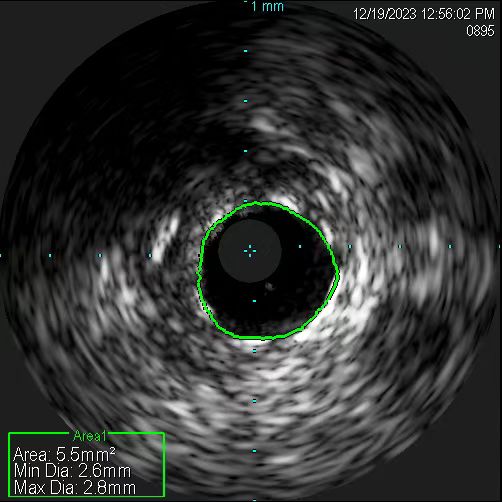

患者手術后的血管。

在無造影劑顯影情況下,冠脈導絲能否送達病變血管遠端,是手術的關鍵一步。操作稍有不慎,導絲就可能誤入分支,也可能穿出血管,引發致命后果。患者及家屬的充分信任,是手術得以進行的先決條件。12月19日11時許,在具備手術條件時,張慧晶帶領手術小組成員開始了挑戰。術前各項準備完成后,韓世飛在李占虎協助下將指引導管順利放置于右冠開口,他依據豐富的手術經驗,將導絲成功送入到右冠遠端,血管內超聲(IVUS)探頭順利到位后便開始進行精準的檢查。結果提示:患者右冠原支架貼壁良好、膨脹充分,進一步證實了此次犯病不是源于右冠。再行前降支IVUS檢查,依靠上次冠脈造影圖像作為參照,指引導管、主支導絲順利到位,反復多次進行IVUS檢查。張宏博根據IVUS圖像及時進行精準的測量,前降支近段最小管腔面積2.7mm2,中段斑塊負荷重,均達到處理標準;遠段血管直徑約2.5mm,近段血管直徑約3mm。張慧晶帶領大家根據IVUS檢查結果,制定了詳盡的支架植入方案:應用血管內超聲的換能器精準測量,輔以分支導絲做為路標,一舉將支架成功釋放到理想位置。最終經IVUS檢查提示:支架膨脹充分、貼壁良好,無殘余狹窄及邊緣夾層。歷時近2小時,手術過程順利,全程未使用一滴造影劑,患者未出現任何不適及并發癥。術后復查心臟超聲較前無變化,無心包積液,確定了無穿孔發生。